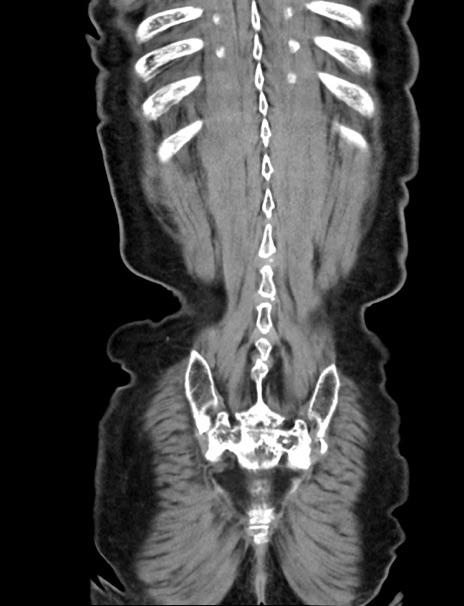

症例33(冠状断像)

【症例】70歳代 女性

【主訴】心窩部痛

【現病歴】延髄病変の精査・加療にて神経内科入院中。本日より心窩部痛あり。

【身体所見】右下腹部を中心に圧痛と反跳痛あり。

【データ】WBC 10900、CRP 0.02